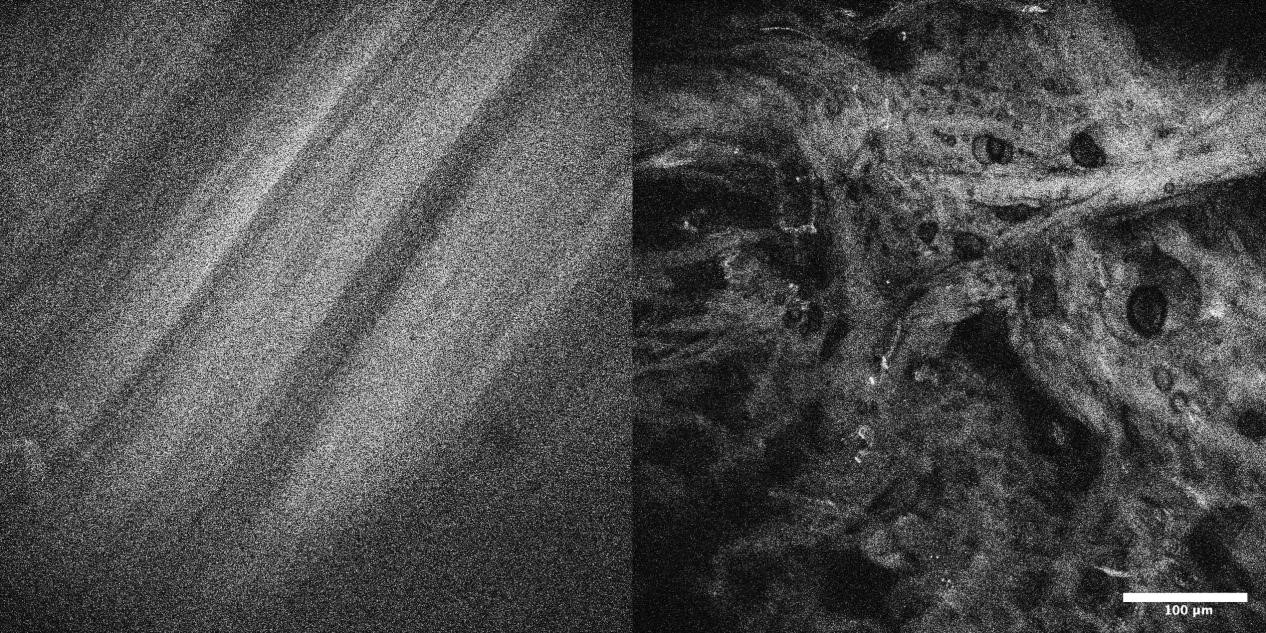

4、自體熒光OptiScan成像

左:ACL中有序的膠原纖維;右:ACL中過(guò)度負(fù)荷后的無(wú)序膠原纖維。

注:前交叉韌帶(ACL)的自體熒光成像。本研究著眼于疲勞相關(guān)微損傷導(dǎo)致的前交叉韌帶失效。Scale bar=100μm。